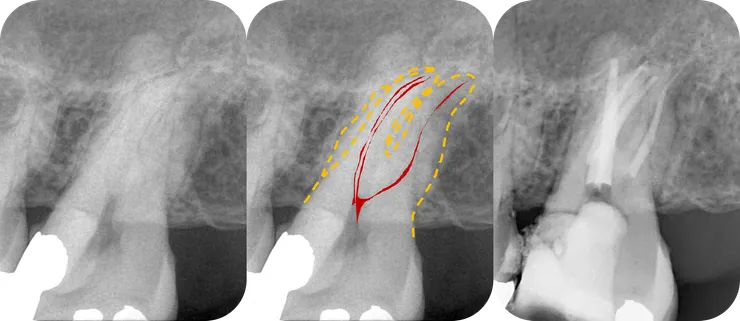

如同開場白強調的,任何 case 在開始前,務必、千萬、一定要先看清楚 root form (橘色虛線) & canal path (紅線)!

就算 canal 鈣化到看不到,也可以依據 root form 來推測出 canal 可能的走向。

果然,從 CBCT 才能看清真相!

(因為 B & D canal 的關鍵點太深了拍不到,因此本篇只 focus 在 ML canal.)

不光是 PA film, 在 CBCT 上我們也可以依據 root form 推測出 canal 的走向 (如下排圖中的紅色標示處)。於是我們可以清楚地看出,先前的路徑 (粉紅色箭頭標示處) 明顯地往 lingual & mesial 偏移,並勘勘在 perforation 前停住......

所以真正的路徑應該會是在舊充填的 DB side.